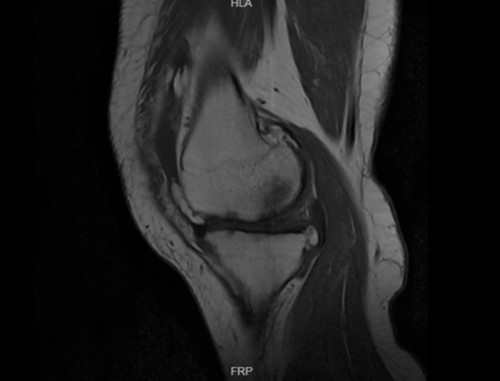

入院后,检查结果出来了,我的膝关节半月板撕裂、髌骨软化、韧带损伤、骨髓水肿,并且有大量积液。我先生的腰椎,包括整个脊柱都有问题,尤其是腰椎间盘突出压迫到坐骨神经,下肢麻木疼痛,让他苦不堪言。